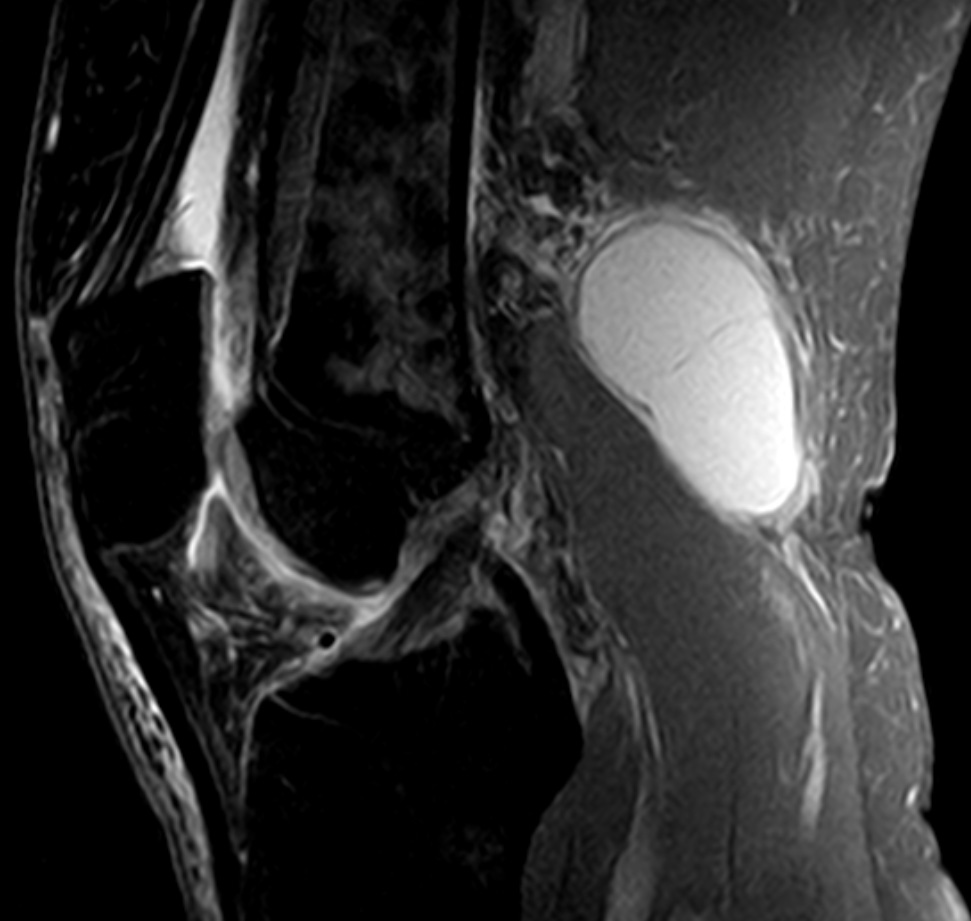

Фото и диагностика кисты Бейкера